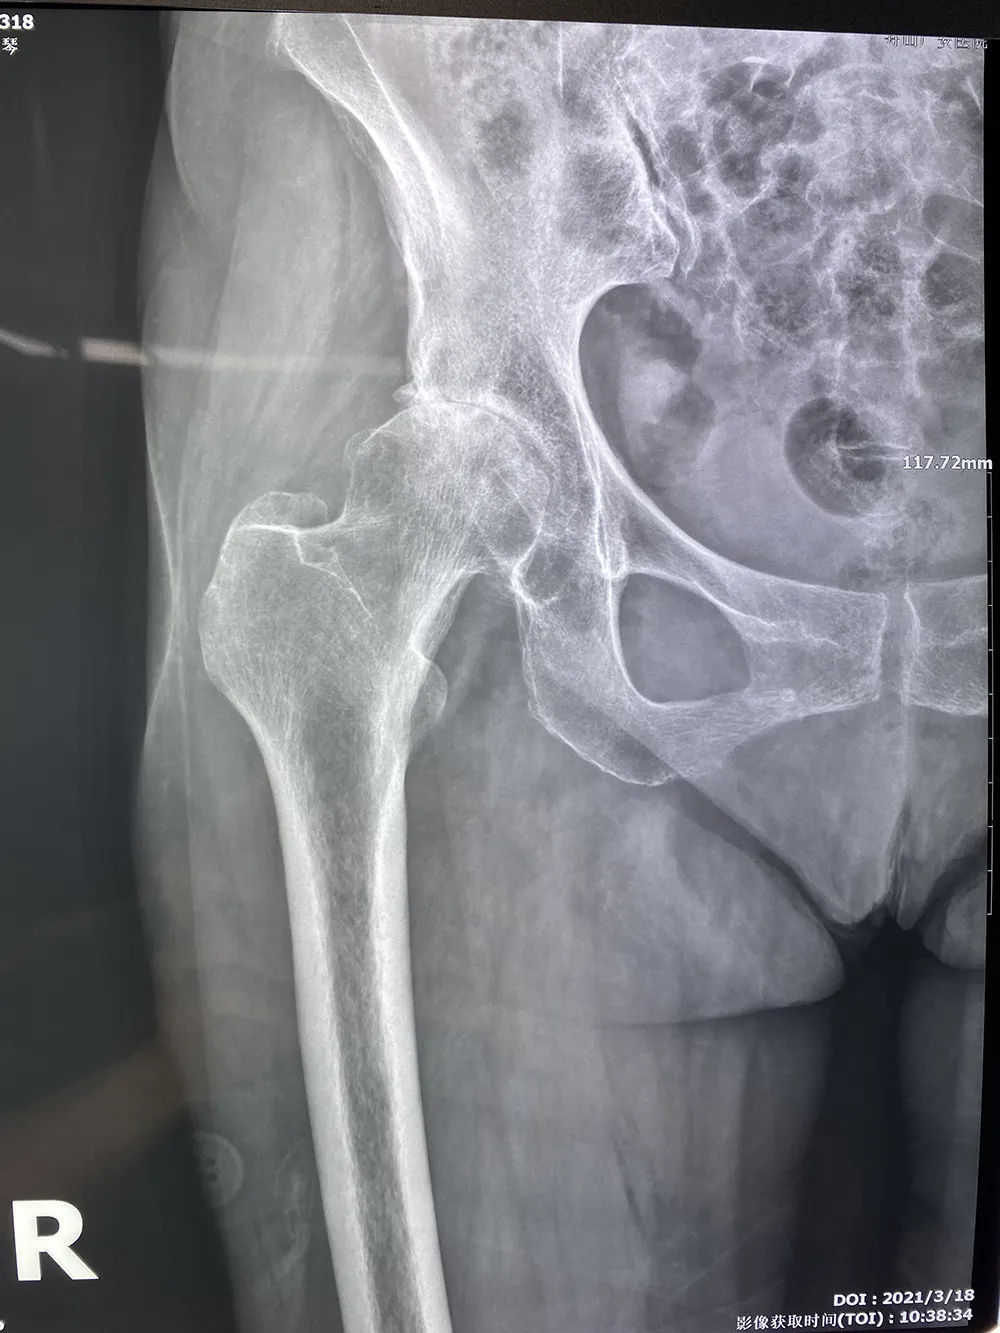

↑術(shù)前拍片提示右股骨頭壞死,髖關(guān)節(jié)骨性關(guān)節(jié)炎